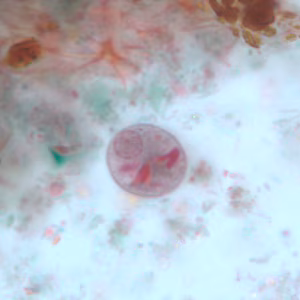

A 45-year-old pig farmer from rural Georgia presented to his health care provider with abdominal pain, cramps and diarrhea. Stool specimens were collected in polyvinyl alcohol (PVA) and 10% formalin for ova and parasite (O&P) examination. The objects in Figures A and B, which measured on average 90 micrometers in length, were observed in low numbers in formalin-concentrated wet mounts of the stool. The objects in Figures C and D, which measured on average 12 micrometers in diameter, were seen in moderate numbers on trichrome-stained slides prepared from the PVA-preserved stool. What is your diagnosis? Based on what criteria?

Figure C